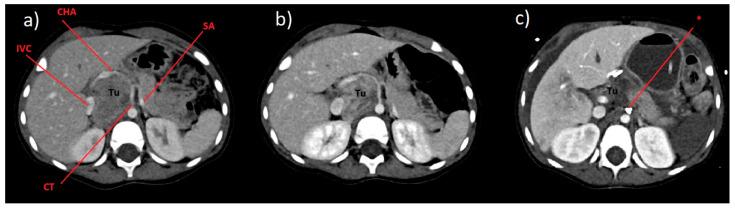

Neuroblastoma is the most common extra-cranial solid tumor in infants and young children, and accounts for approximately 8-10% of all childhood cancers. The International Neuroblastoma Staging System (The International Neuroblastoma Risk Group Staging System (INRGSS)) is based on the age of patient and preoperative imaging, with attention paid to whether the primary tumor is affected by one or more of specific Image-Defined Risk Factors (IDRFs). Patients are classified into the following groups: locoregional L1 and L2 (absent or present IDRFs respectively), M stage (a disseminated form of neuroblastoma) and Ms (the stage present in children younger than 18 months of age with the disease spread to the bone marrow and/or liver, and/or skin). This publication is aimed to present an unexpected complication associated with an accidental ligation of the celiac trunk during resection of a neuroblastoma tumor in a 2.5-year-old boy after initial chemotherapy, initially with vascular IDRFs, stage L2. The consequences of this complication were pancreatic and spleen ischemia and necrosis, and ischemia and perforation of the common bile duct, gallbladder, stomach, and duodenum. Despite detailed diagnostic imaging (computed tomography, magnetic resonance), the presence of vascular IDRFs may result in an unexpected complication in the surgical treatment of neuroblastoma in children.

神经母细胞瘤是婴儿和幼儿中最常见的颅外实体瘤,约占所有儿童癌症的 8-10%。国际神经母细胞瘤分期系统(国际神经母细胞瘤风险组分期系统(INRGSS))基于患者的年龄和术前影像学,注意原发性肿瘤是否受到一个或多个特定的影像定义危险因素(IDRFs)的影响。患者分为以下几类:局限性 L1 和 L2(分别为无或存在 IDRFs)、M 期(神经母细胞瘤的播散形式)和 Ms(18 个月以下儿童的疾病播散到骨髓和/或肝脏和/或皮肤)。本出版物旨在介绍一名 2.5 岁男孩在初始化疗后,在切除神经母细胞瘤肿瘤时,因意外结扎腹腔干而导致的意外并发症,最初存在血管 IDRFs,分期为 L2。该并发症的后果是胰腺和脾脏缺血和坏死,以及胆总管、胆囊、胃和十二指肠缺血和穿孔。尽管进行了详细的诊断影像学(计算机断层扫描、磁共振)检查,但在儿童神经母细胞瘤的手术治疗中,存在血管 IDRFs 可能会导致意外并发症。